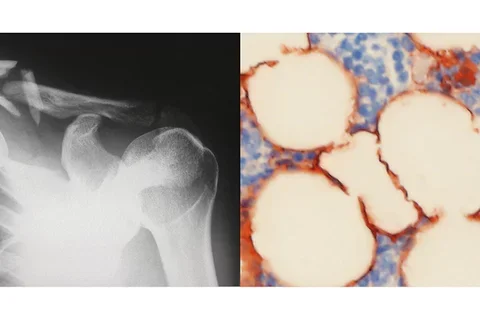

Cells in the bone marrow known as mesenchymal stem cells serve as the building blocks of the body’s skeletal tissues, but whether these stem cells ultimately develop into bone or fat tissues is controlled in part by what are known as epigenetic factors — molecules that regulate genes, silencing some and activating others.

The UCLA researchers, led by distinguished professor Dr. Cun-Yu Wang, chair of oral biology at the dentistry school, demonstrated that when the epigenetic factor KDM4B is absent from mesenchymal stem cells, these cells are far more likely to differentiate into fat cells than bone cells, resulting in an unhealthy imbalance that exacerbates skeletal aging and leads to brittle bones and fractures over time.

To test this, the research team created a mouse model in which KDM4B was absent or removed in several different scenarios. They found that the removal of the enzyme pushed mesenchymal stem cells to create more fat instead of bone tissue, leading to bone loss over time, which mimics skeletal aging.

In addition to age, other environmental factors are thought to reduce bone quality and exacerbate bone loss, including a high-fat diet. The team demonstrated that a loss of KDM4B significantly promoted bone loss and the accumulation of marrow fat in mice placed on a high-fat diet.